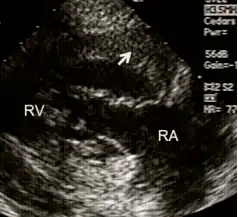

RV inflow view showing marked right ventricular hypertrophy

Echocardiography can be used to directly visualise right ventricular wall thickness. The preferred technique is the trans-oesophageal approach giving a view of 4 chambers. The normal thickness of a right ventricular free wall ranges from 2-5 millimetres, with a value above 5 mm considered to be hypertrophic.[11]